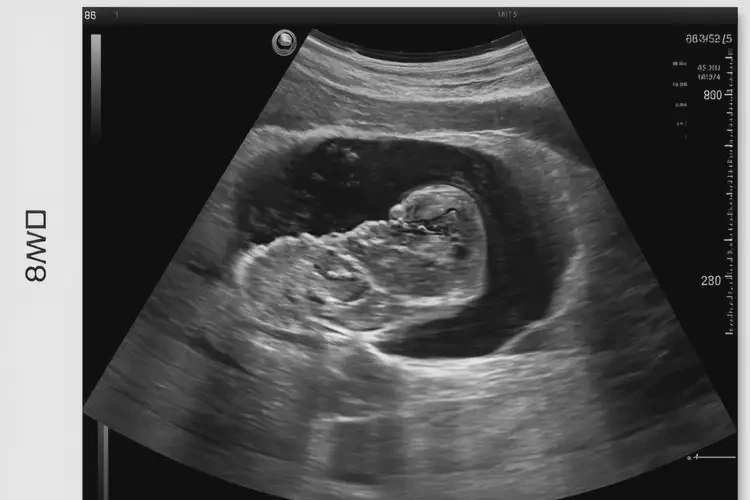

孕8周5天胎心率176寶寶還能要嗎

胎心率176次/分鐘在孕8周5天屬于正常范圍

孕8周5天的胎兒胎心率在176次/分鐘是正常的,無需過于擔(dān)心。胎心率是指胎兒心臟每分鐘跳動(dòng)的次數(shù),通常在孕早期,胎心率會(huì)較快,隨著孕周的增加,胎心率會(huì)逐漸減慢。

孕8周5天胎心率176寶寶還能要嗎(圖1)